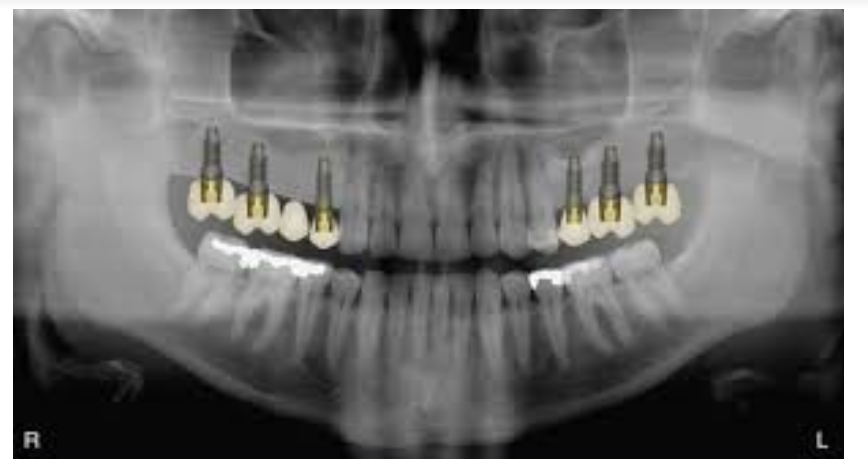

Réhabilitation d’un édentement complet maxillaire à l’aide de six implants (all-on-six):

Dans certaines situations où l’os vient à manquer dans les secteurs postérieurs, on peut à l’aide de 6 implants placés dans le secteur antérieur remplacés les dents jusqu’aux premières molaires sans effectuer de greffes (sinus lift).

Le même procédé est possible à la mandibule avec 6 ou 4 implants (all-on-four).